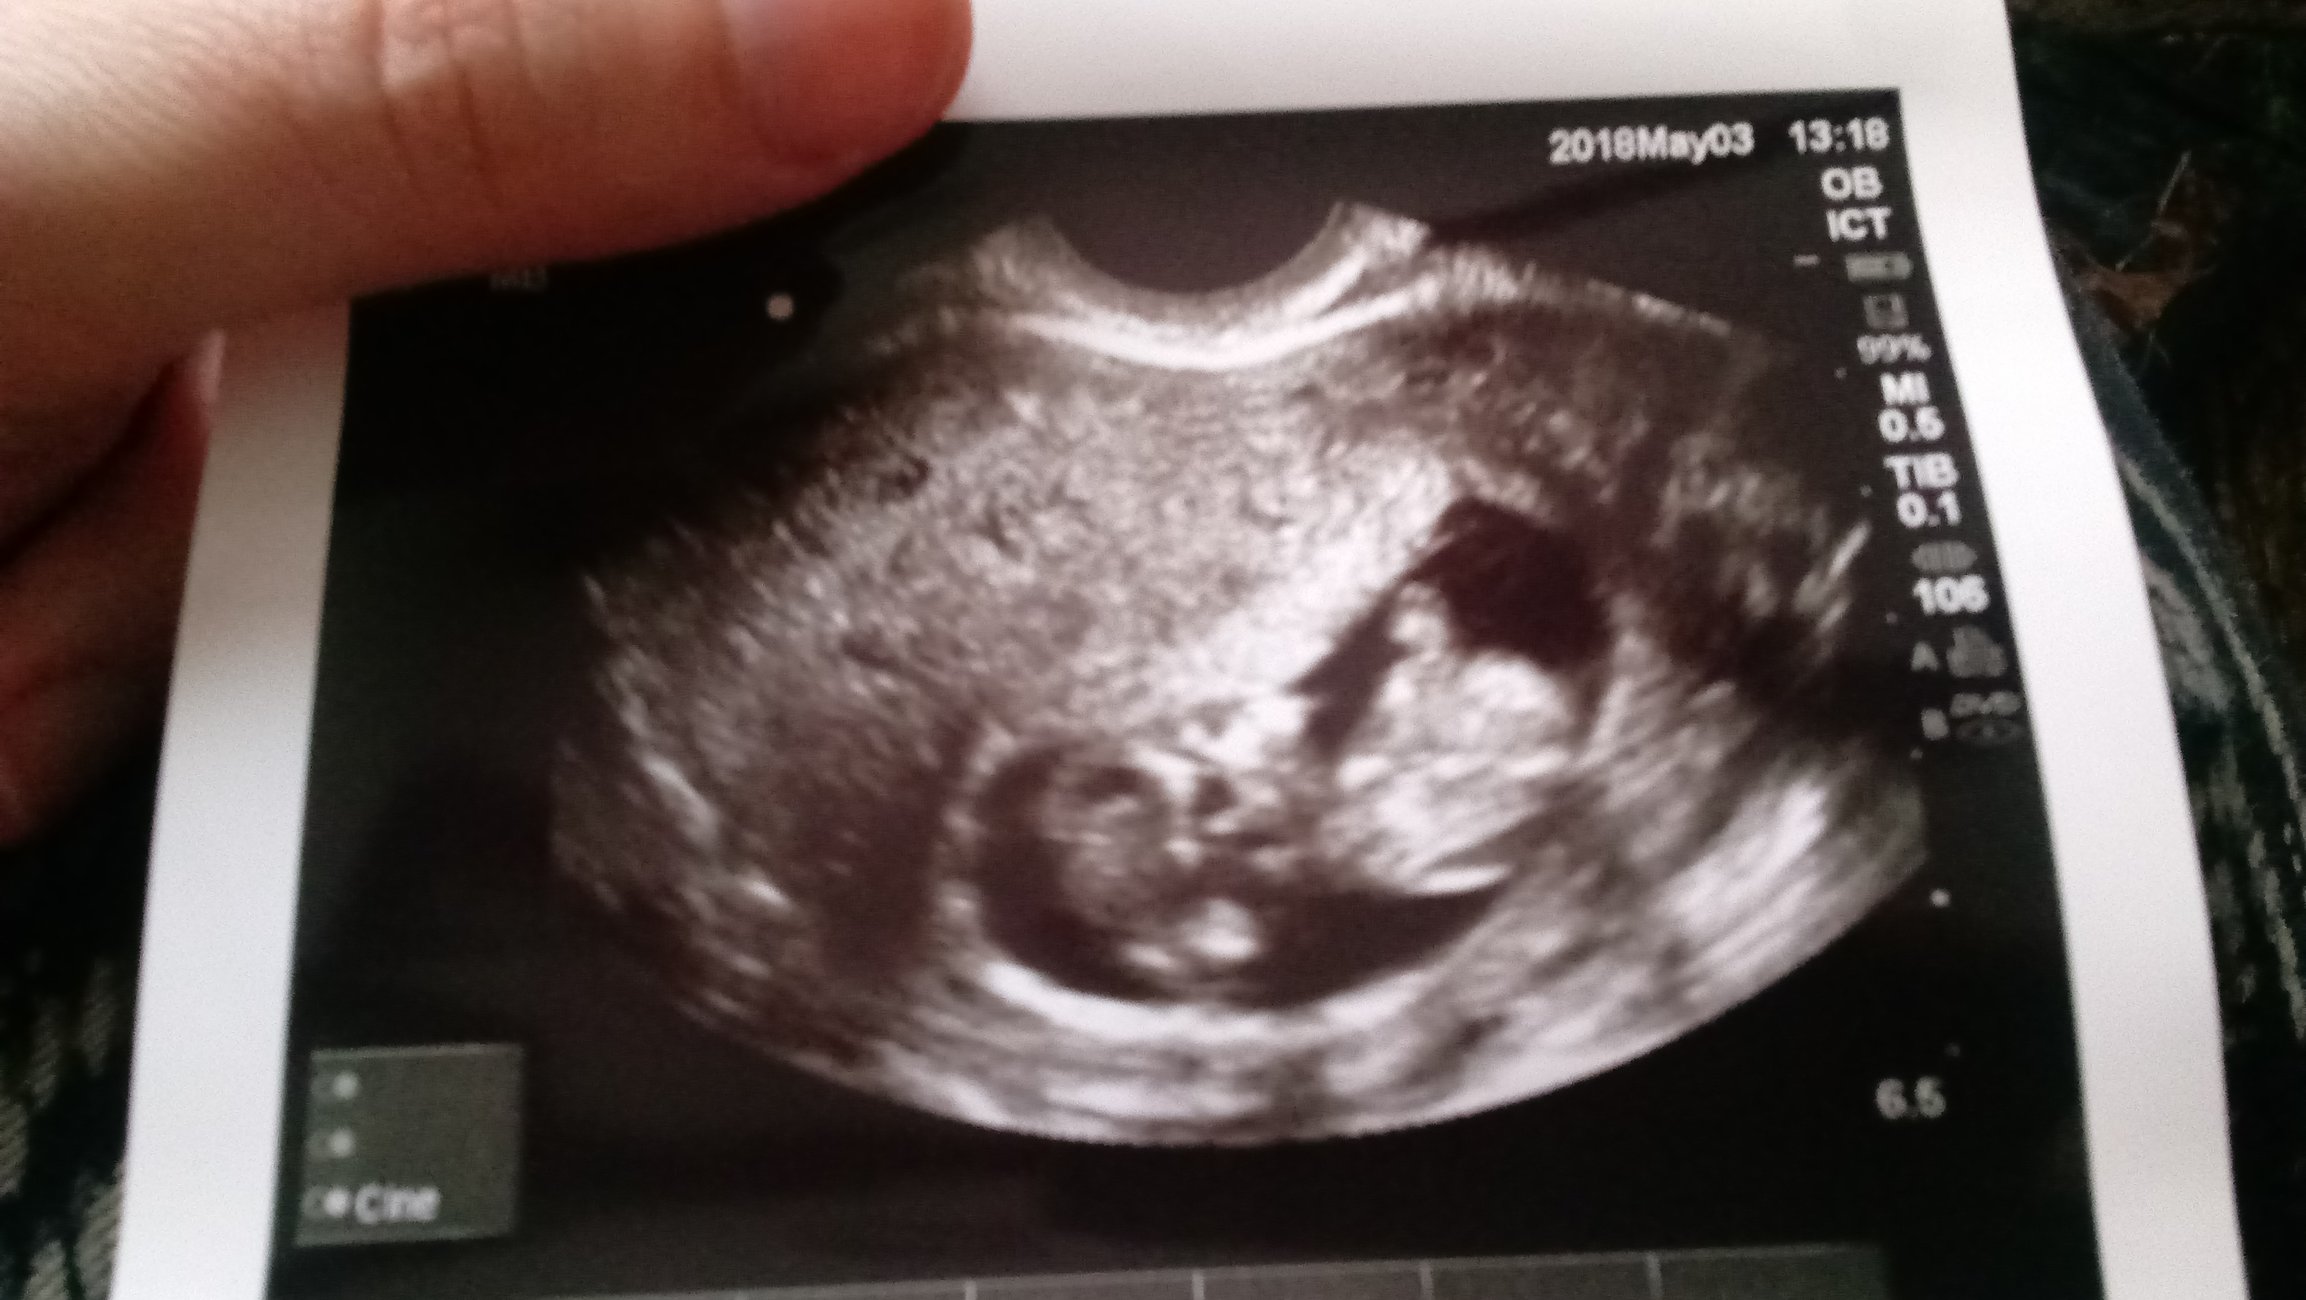

Little Dot is absolutely fine, doing perfect. Heartbeat of 167. Wiggling around and waving. Bleeding apparently might just be a *thing* for me throughout pregnancy. I can't express the amount of relief. Stop scaring your momma LO!!!